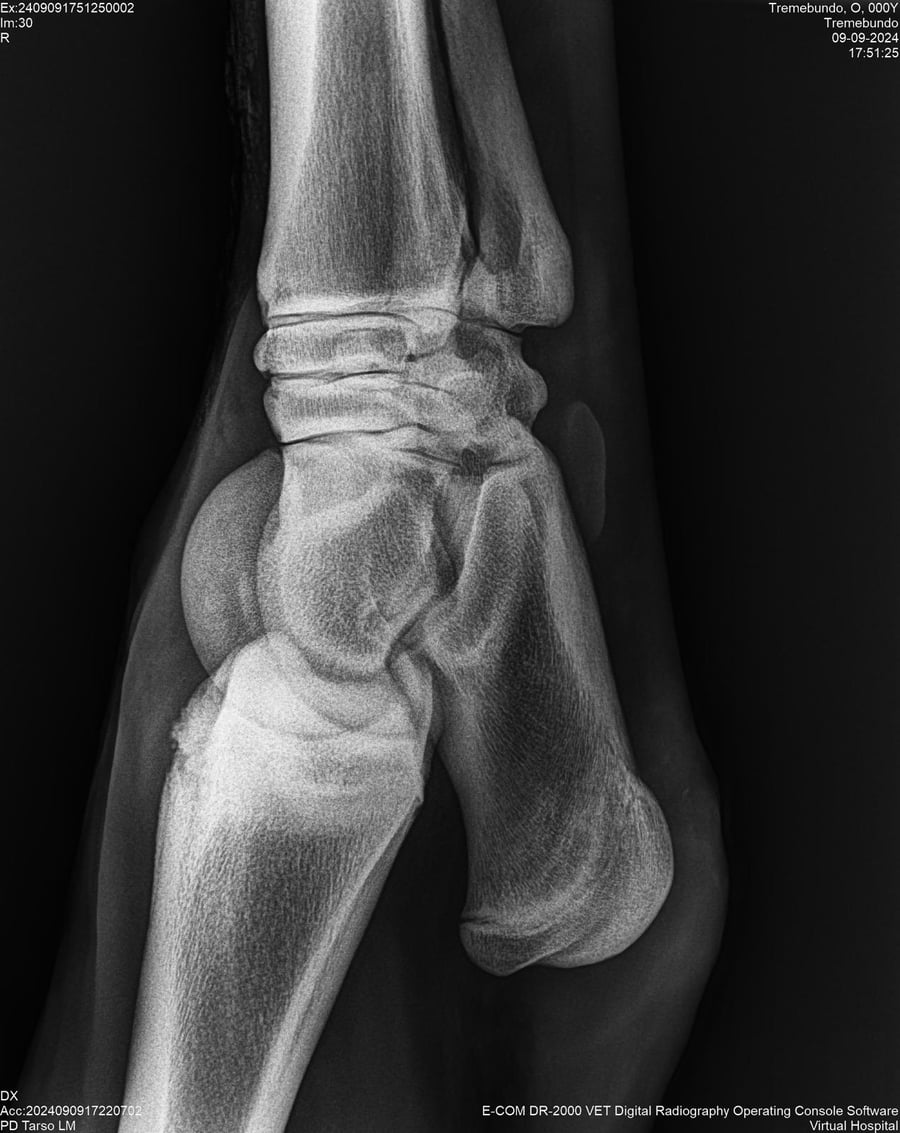

LOTE 37, TREMEBUNDO

Identificador: #291140-

Generacion 2022